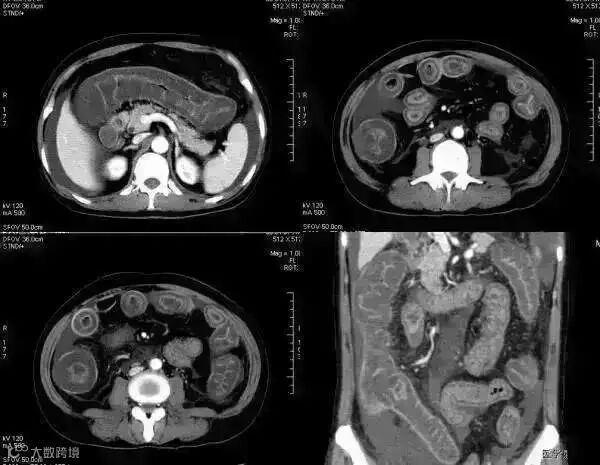

5肠系膜混浊征

肠系膜脂肪受炎症细胞、液体(水肿、淋巴液和血液)、肿瘤浸润及纤维化的CT表现。当肠系膜被液体或细胞浸润时,其脂肪CT值增加到-40~ -60HU(肠系膜脂肪的CT值类似于皮下及腹膜后脂肪,约-100~-160hu,肠系膜血管常呈横行或断面显示。),动、静脉失去锐利边缘。根据浸润的性质和范围,肠系膜血管可部分或完全模糊,顺着脏层腹膜常能发现肠系膜疾病的线索,在周围脂肪衬托下,肠系膜病变显示更加清晰。

上两幅图:肠系膜上动脉栓塞

下两幅图:十二指肠扭转致肠壁增厚、肠系膜水肿